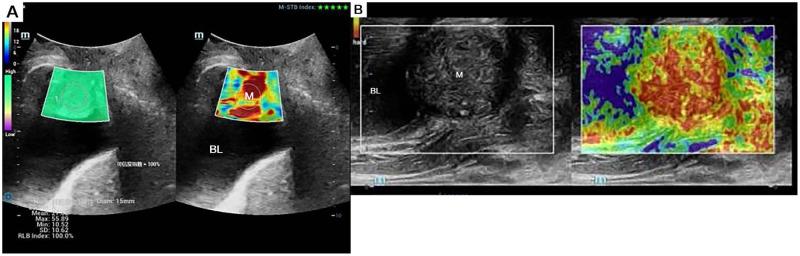

While histopathology remains the diagnostic gold standard for urothelial carcinoma, this case highlights the emerging role of advanced ultrasonographic techniques in characterizing urethral malignancies. We present a 51-year-old female with a one-month history of refractory lower urinary tract symptoms (urinary frequency, urgency, dysuria, and nocturia) unresponsive to conventional anti-inflammatory therapy. Multimodal ultrasonographic evaluation, incorporating conventional sonography, transrectal ultrasound, elastography, and contrast-enhanced ultrasonography (CEUS), revealed a complex proximal urethral mass with malignant features. Subsequent cystoscopic and histopathological examinations confirmed the diagnosis of primary urethral adenocarcinoma. This case underscores the diagnostic value of comprehensive ultrasound protocols in evaluating female urethral neoplasms.

虽然组织病理学仍然是尿路上皮癌的诊断金标准,但该病例凸显了先进超声技术在尿道恶性肿瘤特征描述方面日益重要的作用。我们报告一名51岁女性,有1个月难治性下尿路症状(尿频、尿急、尿痛和夜尿)病史,对传统抗炎治疗无反应。多模态超声评估,包括传统超声、经直肠超声、弹性成像和对比增强超声(CEUS),发现近端尿道有一个具有恶性特征的复杂肿块。随后的膀胱镜检查和组织病理学检查确诊为原发性尿道腺癌。该病例强调了综合超声方案在评估女性尿道肿瘤中的诊断价值。